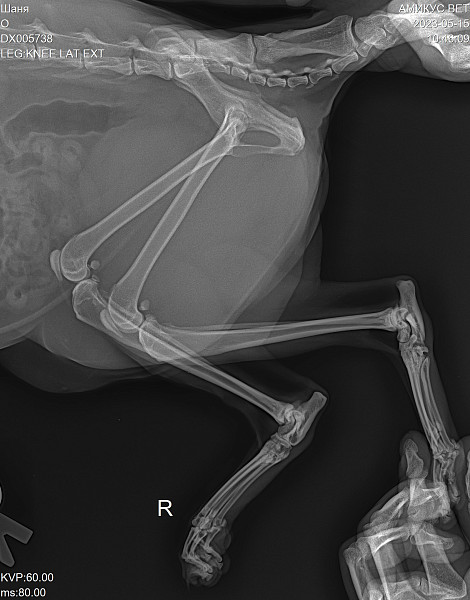

Рентгеновские снимки анатомии собак: строение и здоровье